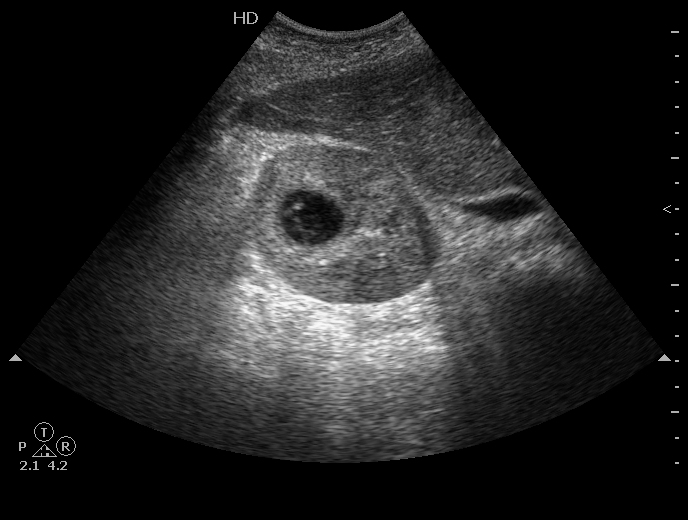

Мужчина средних лет, из хирургического отделения с диагнозом правосторонняя почечная колика.

Это было 8 месяцев назад. ОАК в норме. В ОАМ эритроциты. Температура тела была нормальная. Я написала "Tumor павой почки. Уретерогидронефроз справа". Приступ купировали, пациента выписали и отправили в онкодиспансер. Там повторили УЗИ (в карточке я его не нашла) и, как сказал пациент, написали всё то же самое. Через 2 недели ему выполнили МСКТ : МСКТ-признаки кисты правой почки категория 2 по Bosniak.

И вот спустя 8 месяцев:

УЗ-семиотика в пользу некротического очагового процесса, который локализован в области сосочка и пирамиды.

Почему я спрашивал про причину обструкции. Это мог быть камень, далее - гнойный очаговый пиелонефрит. Это мог быть некроз пирамиды с отторжением сосочка и блоком мочеточника. Содержимое полости скорее всего дренировалось в ЧЛС.

Но для первого и второго вариантов должна быть соответствующая клиника, а для второго варианта - и причина.

На практике чаще всего встречается первый вариант, поэтому исхожу из него.

На кисту с нагноением или кровоизлиянием не похоже. Нет стенок, характерных для кисты. И она не должна исчезать при повторном исследовании.